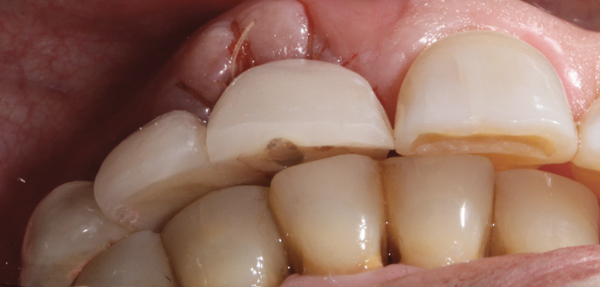

Fig 4. Flared abutments (healing or definitive) that encroach on the biologic width of the peri-implant bone will also result in apical remodeling. This is likely to compromise the critical crest of bone on the adjacent teeth that is largely responsible for supporting the papilla.

Figure 4

In order to maximize the height of the peri-implant papilla, significant efforts must be made to maximize the blood supply and to preserve the bone on the adjacent roots and between the implant.12 Pressure and blanching of the peri-implant tissues compromises the blood supply of this fragile complex and (eventually) leads to reduction in the height of the papilla (Figure 3). At a given site in a given individual, there is a natural biologic width that the body will strive to maintain between any bone and any non-integrated material. Thus, if a non-integrating abutment is placed within close proximity to the bone on the adjacent natural tooth (Figure 4), inevitably the bone will be remodeled to a more apical position to re-establish the biologic width. This distance obviously varies, but generally 1 mm to 1.5 mm is needed.13